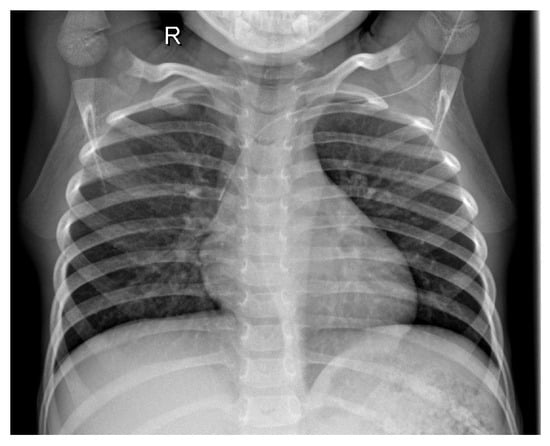

3.1. Dataset

3.2. Preprocessing